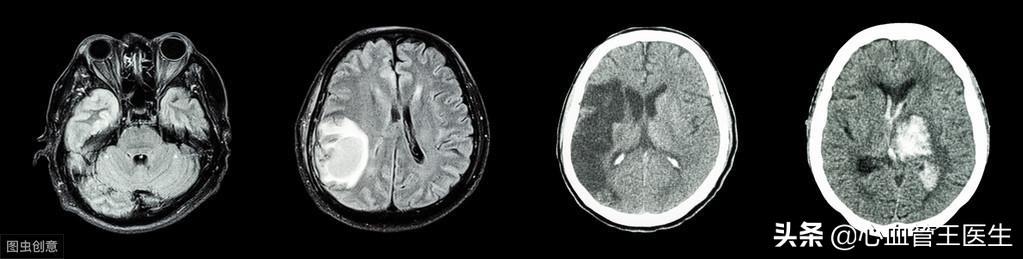

実際、脳出血と脳梗塞は同じような経過をたどることが多く、症状との区別が難しいので、病院でCTを撮ってはっきりさせなければならない。

もちろん、脳卒中には脳梗塞と脳出血があるため、高血圧による脳血管障害のリスクは脳出血だけに向けられたものではありません。 脳梗塞は、高血圧によって脳動脈の動脈硬化が進み、プラークが形成され、脳血管が閉塞して脳梗塞を起こすものであり、脳出血は、長期間の血圧上昇によって脳動脈がもろくなったり、弾力性が低下したり、微小動脈瘤が形成され、脳血管の容量を超える圧力がかかって血管破裂を起こすものです。血管破裂。脳血管が破裂すると、大量の血液が頭蓋腔に流入して脳組織を圧迫し、頭痛、嘔吐、意識障害などの症状が現れます。脳出血は危険因子の高い合併症であり、脳出血発生後30日以内の死亡率は35~52%と高く、同時に弊害の大きい合併症でもあり、6ヵ月後には約80%の患者が自己管理能力を回復できない。 したがって、脳出血は高血圧患者にとって予防すべき合併症であり、血圧を下げることが脳出血の危険性を減らす主な対策となる。